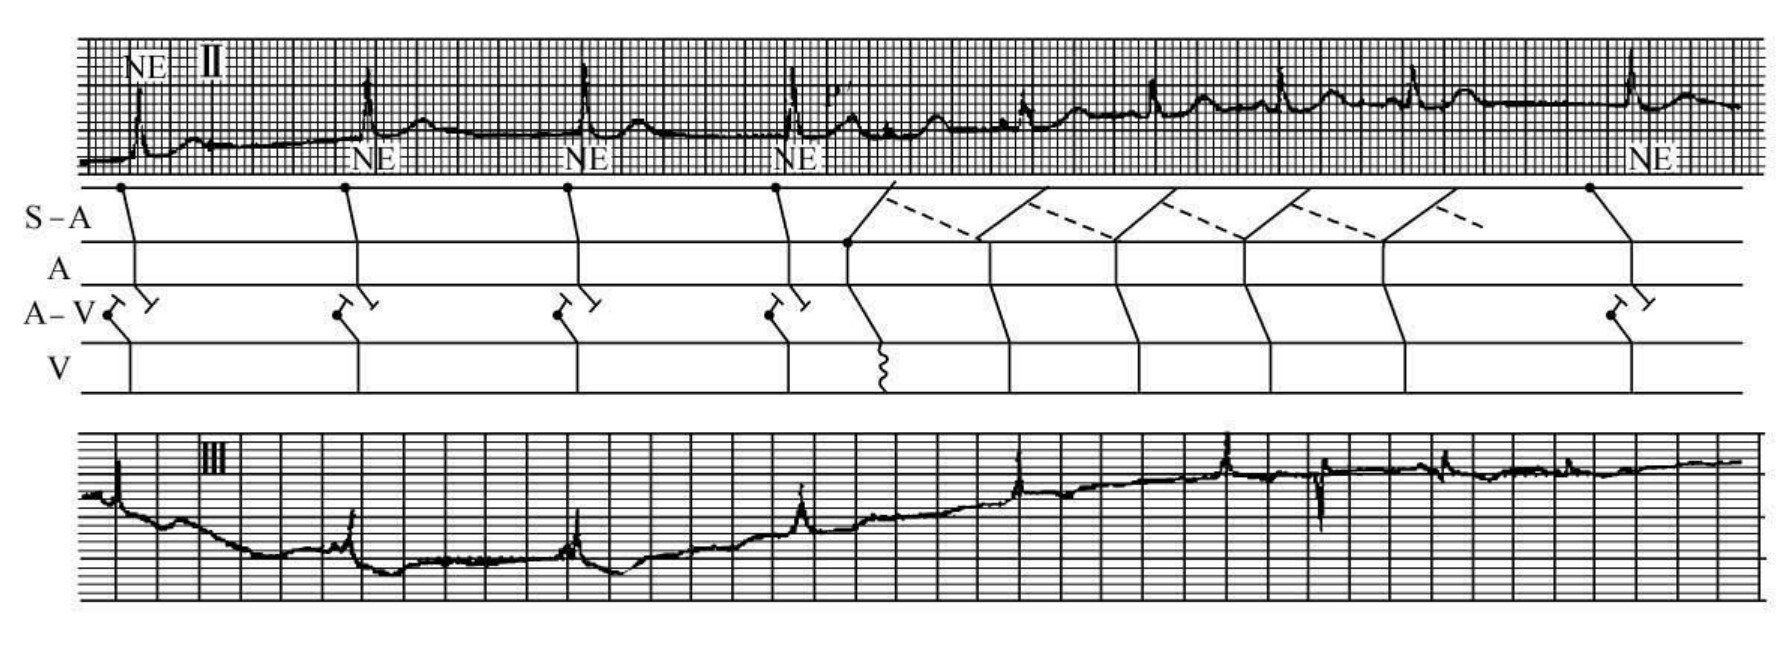

图37-11 房性期前收缩诱发窦房折返性心动过速

患者女性,44岁,临床诊断:病窦综合征,双结病变。全图Ⅱ和Ⅲ导联基本上呈现为窦性心律与房室交接性逸搏心律共同形成的干扰性房室分离的心电现象。Ⅱ导联R4的T波顶峰有一房性P'波并下传心室产生室内差异性传导的QRS波,此后连续出现4个“窦性P波”,皆以正常的P-R间期下传心室,为房性期前收缩诱发窦房折返性心动过速,Ⅲ导联的后半段亦有类似上述现象